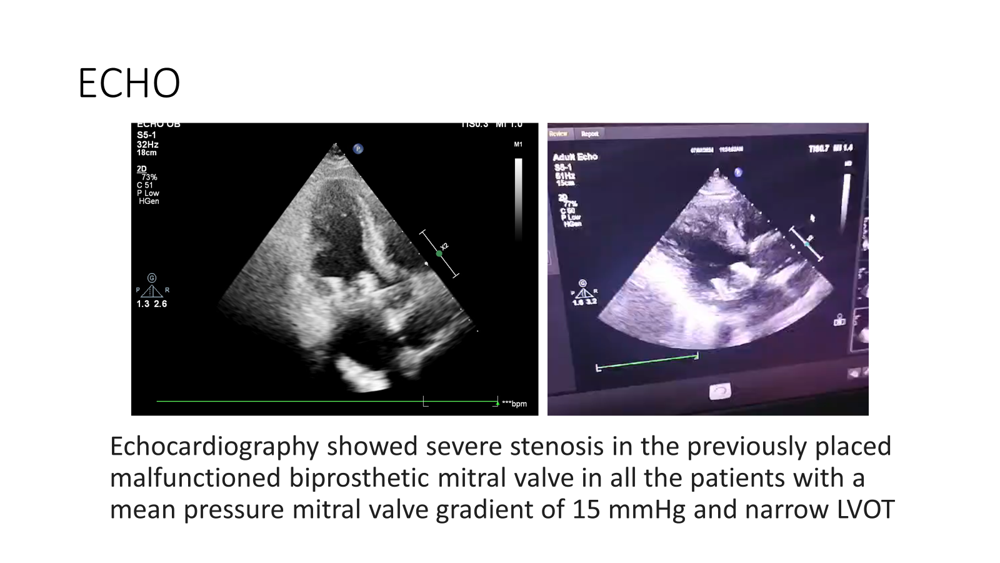

Relevant Test Results Prior to Catheterization

Considering his overall surgical risk—with a Society for Thoracic Surgery (STS) score ranging between 4.2 and 6.2, and a preoperative mean mitral valve pressure gradient of 12–18 mmHg—a redo MVR would have been a high-risk surgery. Therefore, a Lampoon-assisted TMVR was planned."